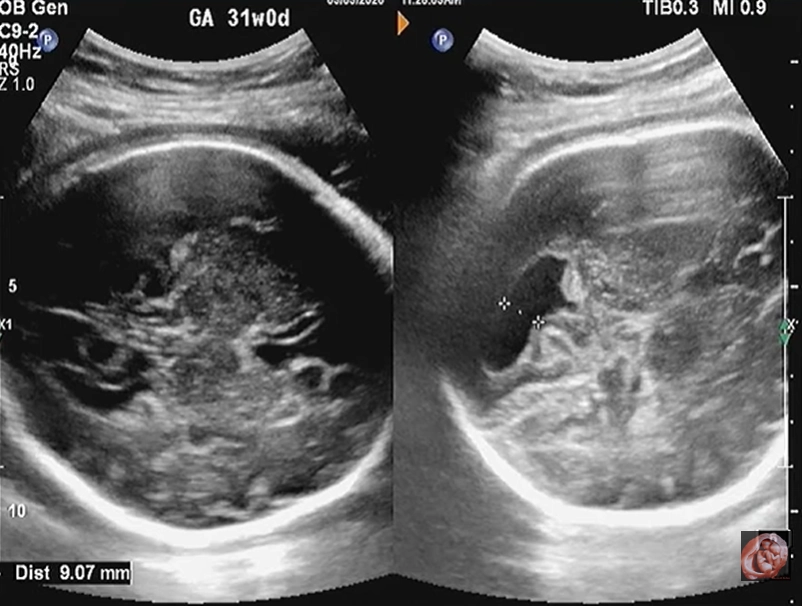

Cứng đa khớp bẩm sinh (Arthrogryposis Multiplex Congenita - AMC)/Chuỗi biến dạng do thai nhi bất động/giảm động (Fetal Akinesia/Hypokinesia Deformation Sequence - FA(H)DS)